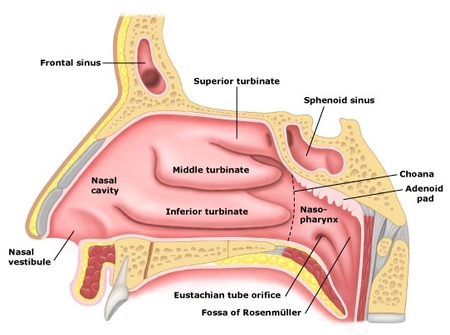

코 구조는 대개 1~3일 잠복기를 거쳐 전구기 증상이 나타납니다.바이러스 침범에는 국소적인 건조감, 작열감 또는 가려움증 등이 느껴지며 전신적으로 불쾌감, 미열, 한기, 근육통, 두통 등이 유발됩니다.카타르기가 시작되면 전신 증상이 심해지고 다량의 맑은 콧물, 코막힘, 후각 소실이 나타납니다.

경희미의원 코내시경, 비내시경, 경상코점막의 발적을 관찰하여 2차 세균 감염이 일어나지 않을 경우 점액기로 옮김과 동시에 호전됩니다.통상적으로 증상이 사라지기까지 5~10일 소요됩니다.